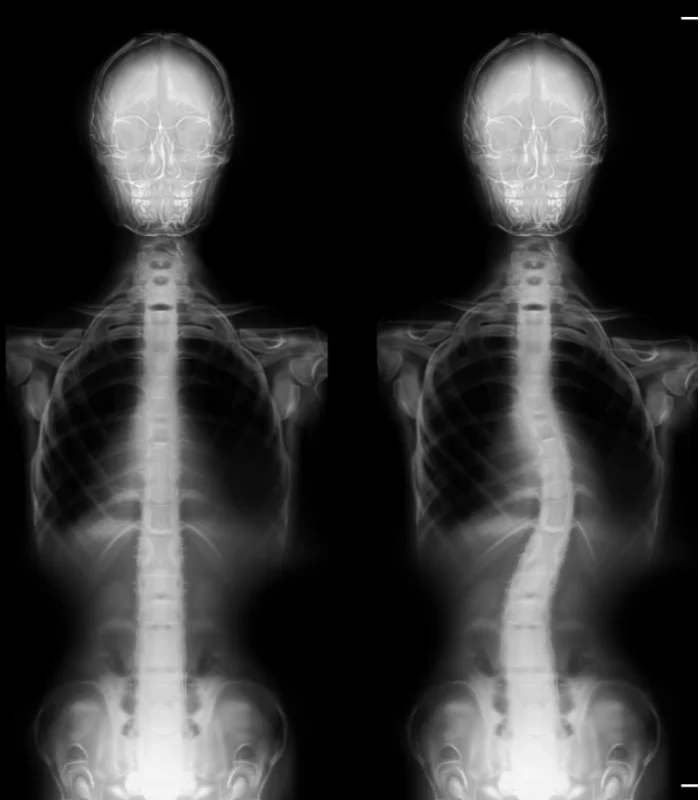

Scoliosis manifests as an abnormal bend or curve in the spine, deviating from the ideal vertical alignment of a healthy spine. The exact origin of this curve can often be elusive. In its early stages, it may begin as a minor bend due to a single vertebra's misalignment. Over time, the body compensates by developing musculature that continues to pull the spine into lateral curves to maintain a level head position.

Often, parents or close associates are the first to notice scoliosis, as the shoulders and pelvis no longer appear level. A thorough physical examination assesses gait and utilizes visual and manual evaluations to determine the extent of spinal curvature. An Adams Position Test, involving the patient bending forward as far as possible, can reveal the presence of an issue. If a noticeable curvature is detected, an X-ray will be employed to assess the severity of scoliosis.